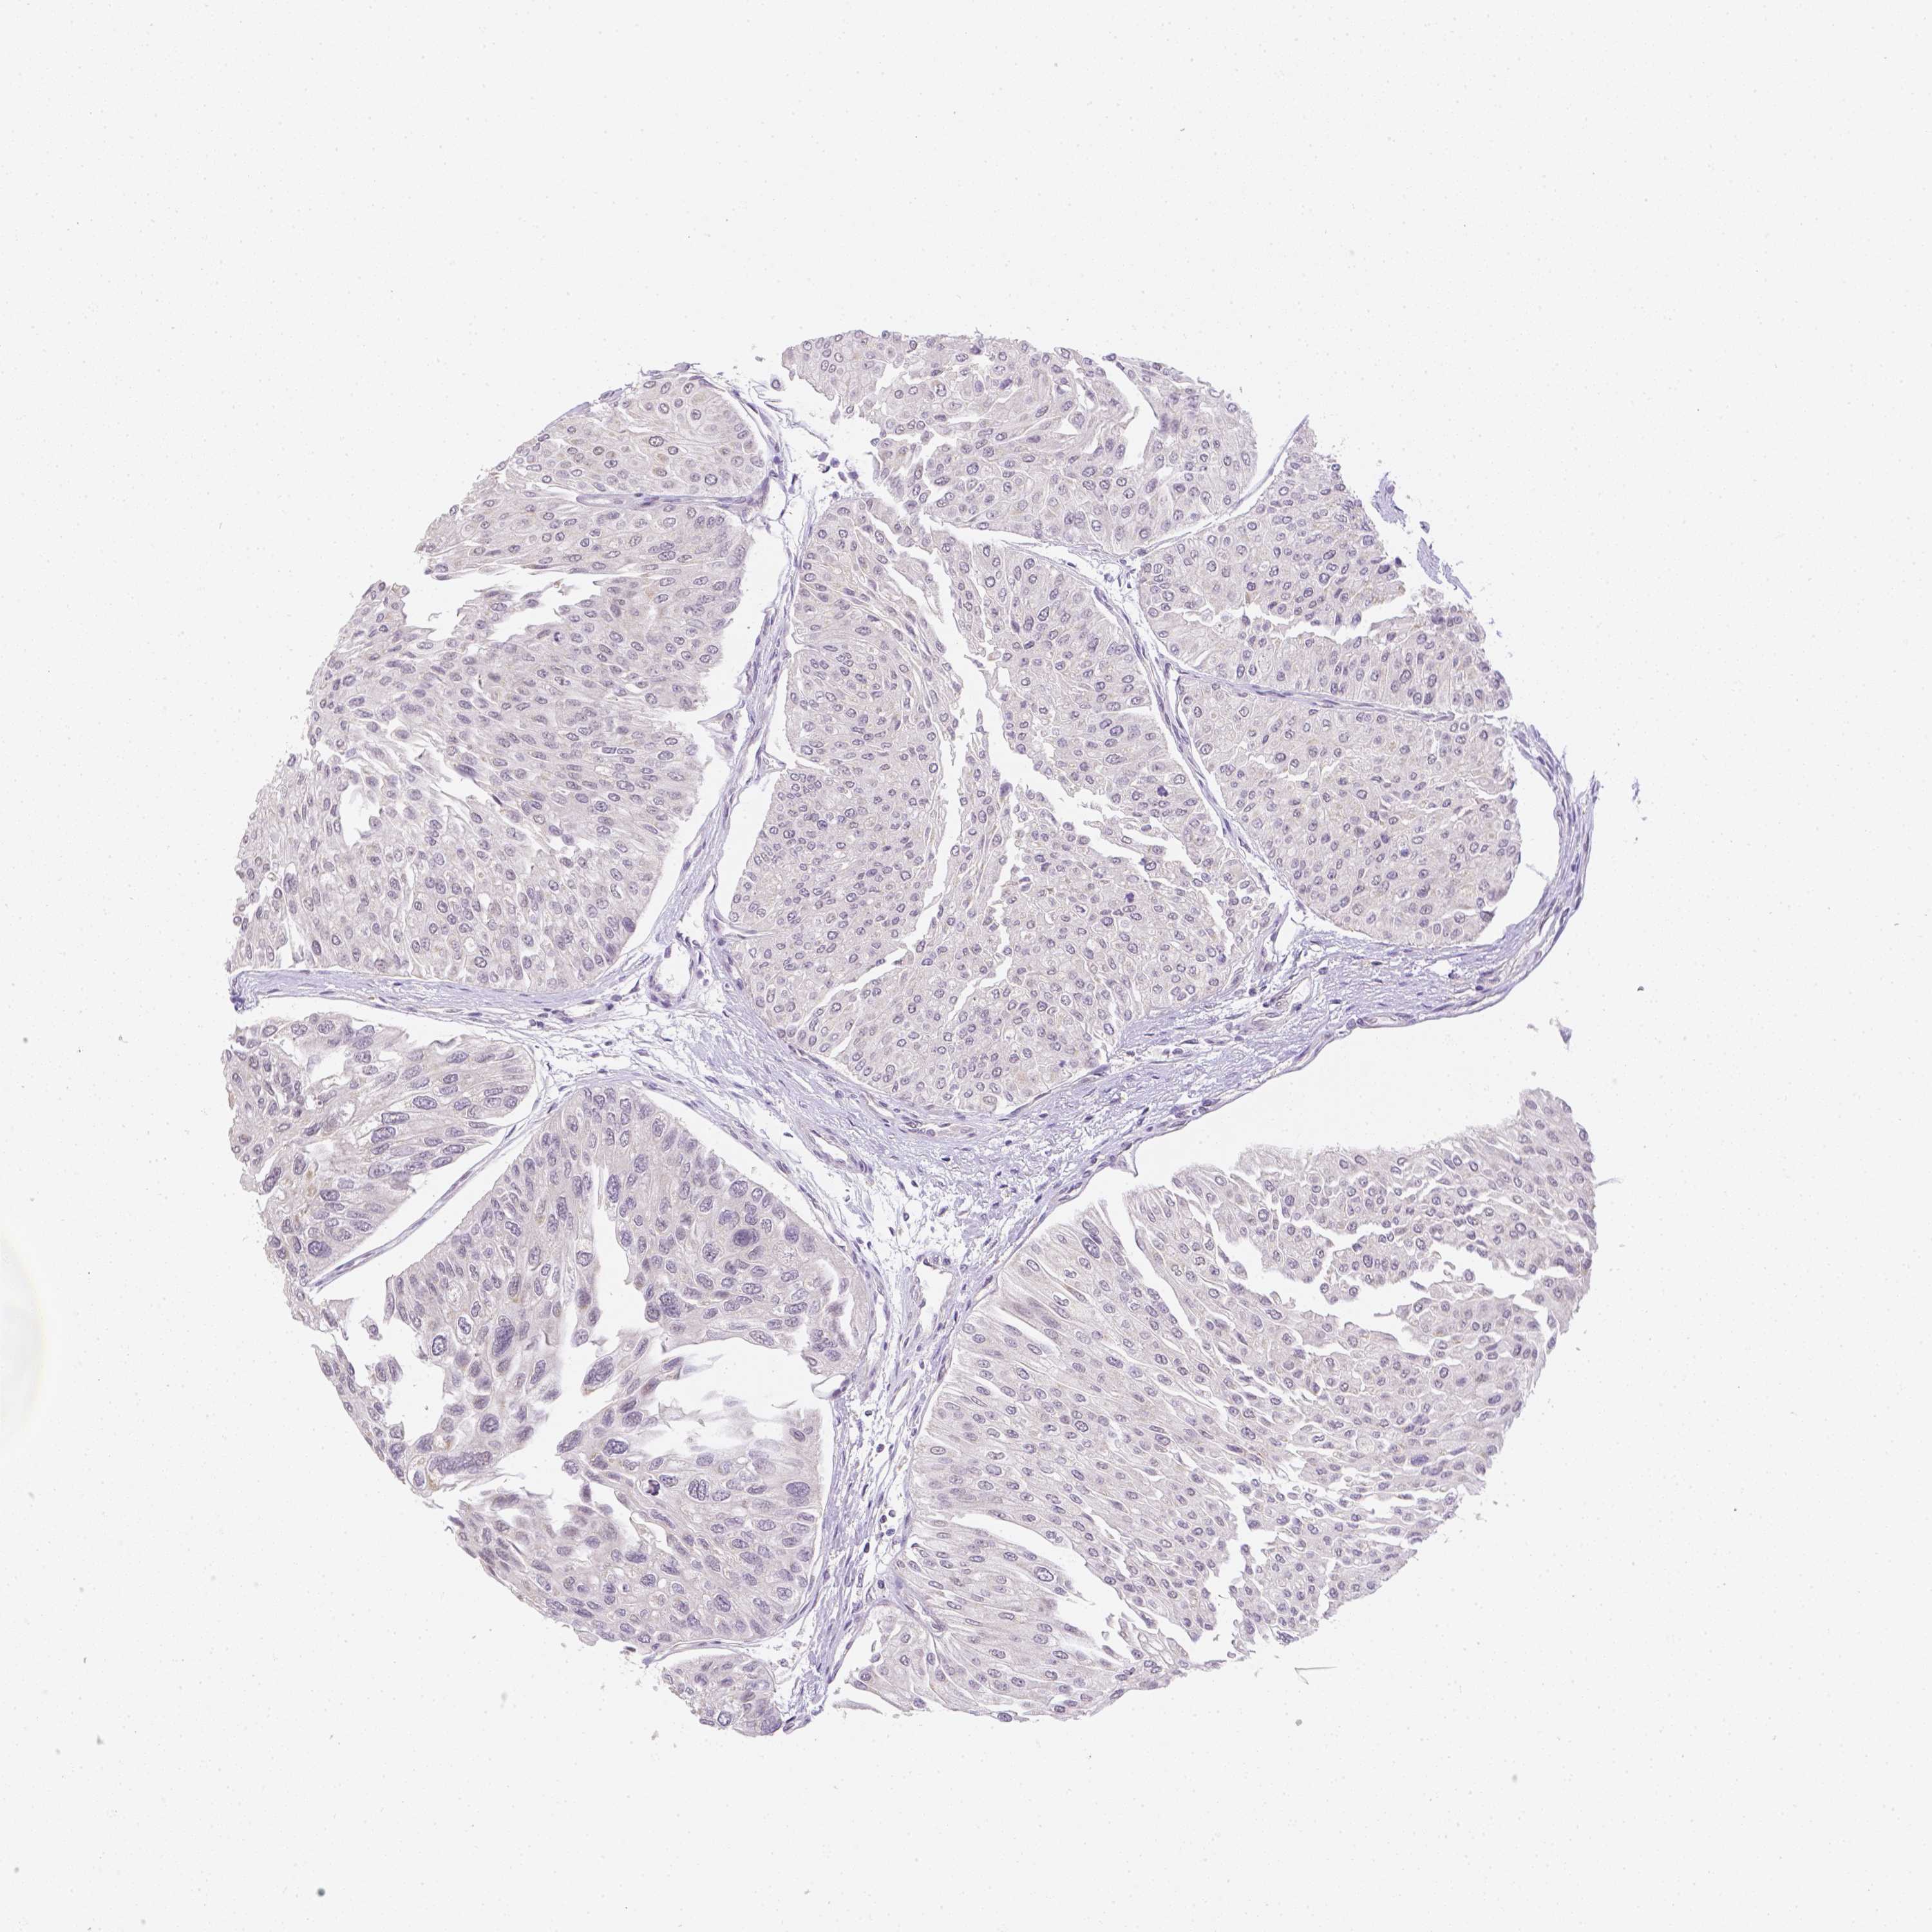

UROTHELIAL CANCER - Protein expressioni

A mouse-over function shows sample information and annotation data. Click on an image to view it in a full screen mode. Samples can be filtered based on level of antibody staining by selecting one or several of the following categories: high, medium, low and not detected. The assay and annotation is described here.

Note that samples used for immunohistochemistry by the Human Protein Atlas do not correspond to samples in the TCGA dataset.

Antibody stainingi

Antibody staining in the annotated cell types in the current human tissue is reported as not detected, low, medium, or high, based on conventional immunohistochemistry profiling in selected tissues. This score is based on the combination of the staining intensity and fraction of stained cells.

Each image is clickable and will lead to virtual microscopy that enables deeper exploration of all samples and also displays staining intensity scores, fraction scores and subcellular localization as well as patient and tissue information for each sample.

Antibody HPA059519

Staining

High

Medium

Low

Not detected

Intensity

Strong

Moderate

Weak

Negative

Quantity

>75%

75%-25%

<25%

None

Location

Nuclear

Cytoplasmic/membranous

Cytoplasmic/membranous,nuclear

Urothelial carcinoma, High grade

Urothelial carcinoma, Low grade

Urothelial carcinoma, NOS